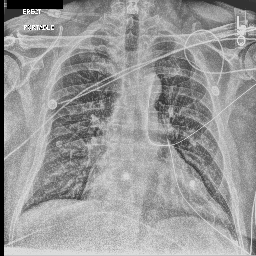

Refer to caption

Figure 1: A chest X-ray and its associated report written by a radiologist.

Diagnostic radiology is the medical field of creating and evaluating radiological images (radiographs) of patients for diagnostics. Radiologists are trained to simultaneously identify various radiological findings (e.g., diseases), according to the details of the radiograph and the patient’s clinical history, then summarize these findings and their overall impression in reports for clinical communication (Kahn Jr et al., 2009; Schwartz et al., 2011). A report typically consists of sections such as history, examination reason, findings, and impressions. As shown in Figure 1, the findings section contains a sequence of positive, negative, or uncertain mentions of either disease observations or instruments including their detailed location and severity. The impression section, by contrast, summarizes diagnoses considering all report sections above and previous studies on the patient.